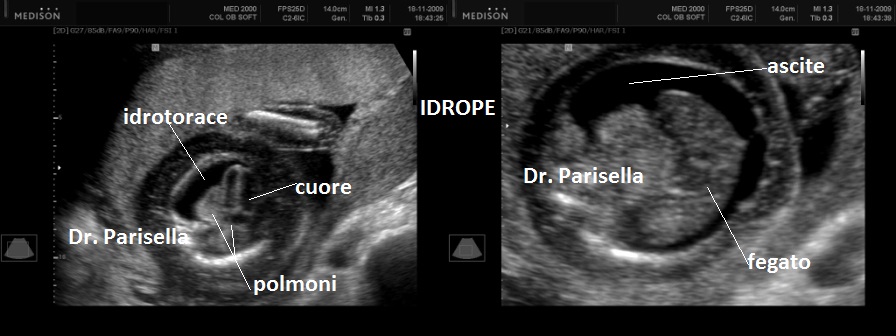

4) idrope .